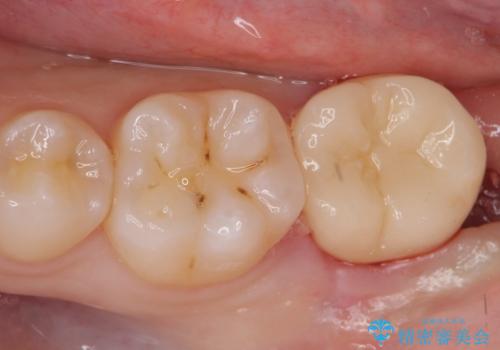

奥の虫歯 ジルコニアクラウンでの修復